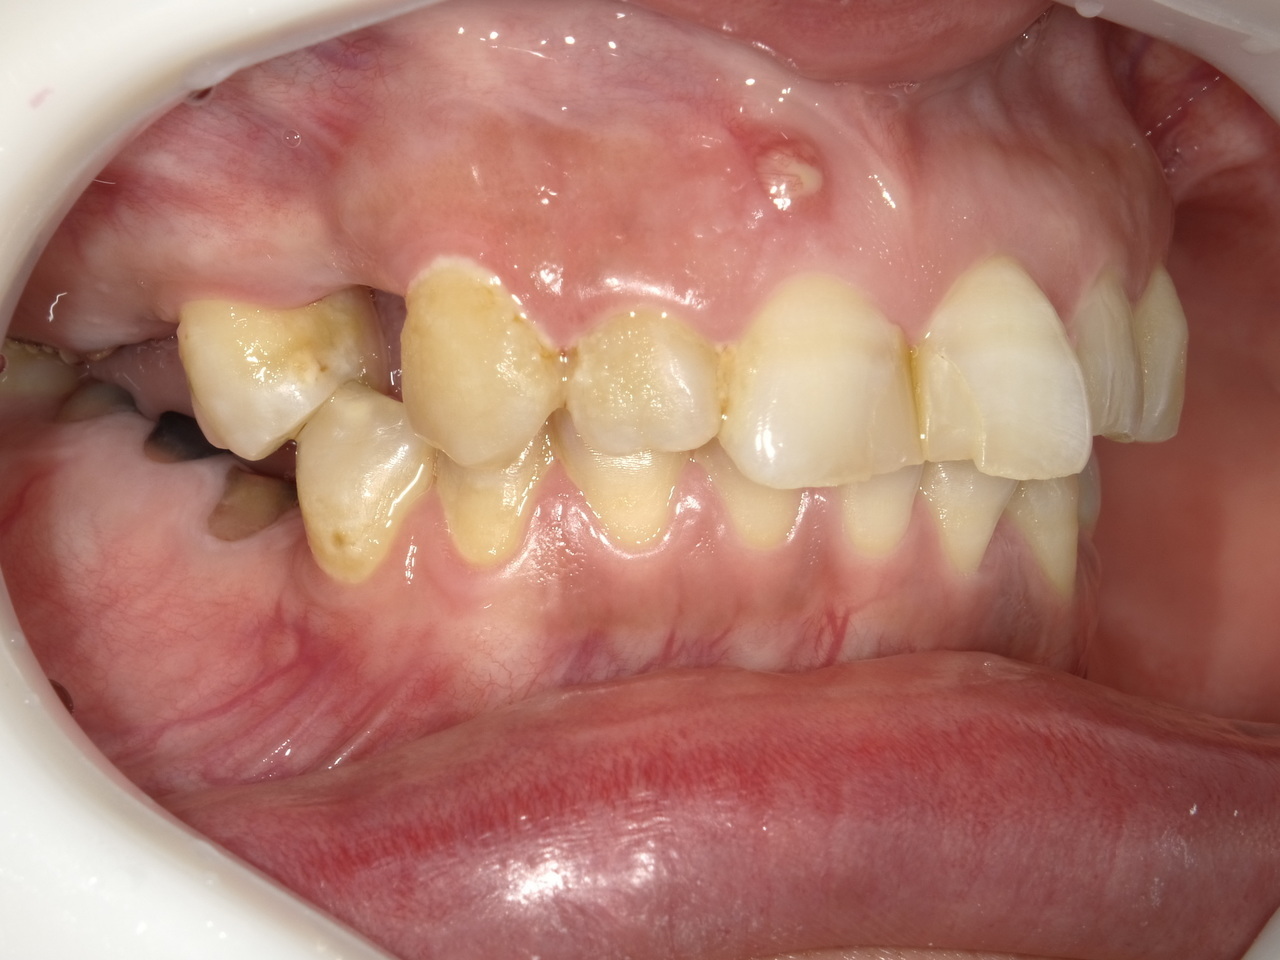

Before

枚方市のインプラントの症例

E・S様 女性 60代

患者様の症状としては、左上5番の排膿と重度の歯の動揺、重度の骨吸収、左上3番、中程度の骨吸収と中程度の歯の動揺、自発痛がありました。

治療法としては、左上3456にブリッジ治療が行われていたが、左上5の骨吸収と排膿を認めるために抜歯を行った2か月後に、患者様は、インプラント治療を希望。左上3の骨吸収と動揺も認めていたために、左上3を保存しても将来的な抜歯が予想されたため、左上3抜歯しての左上345の3ユニット式ブリッジ治療の計画を立てインプラント手術を行っています。患者様は、前歯がないことを気にされていたため、左上3番の抜歯と同時の仮歯製作と左上4番暫間インプラントにての仮歯製作を手術と同時に行っています。また、左上3番の歯肉退縮を予防するために、ご自分の歯の一部を温存するルートメンブレンテクニックを行っています。左上5に関しては、既存骨が3mm程度しかないので、グラフトレスサイナスリフトを施行して、表面の骨吸収した部分に骨補填材填入して、ボリュームを維持させていただいています。最終的な3ユニットブリッジは、ジルコニアで製作しています。補綴物の製作に関しては、オールデジタルで行っています。

治療結果は、患者様の希望通り、見えるところの歯がない状態なく、治療を終えることができたことと、また、グラフトレスサイナスリフトを施行することにより、従来のサイナスリフトを施行した場合と比較して、6時か月以上早く治療を終えることができたことと、ルートメンブレンテクニックを行うことで、歯肉退縮を少なくでき、自然な見た目で、最終補綴物を装着できました。従来のGBRやサイナスリフトを行わなかったことにより、短時間で、低侵襲に治療を終えることができ、審美面と機能面の回復を行うことができました。

治療の期間・回数:4か月、10回

治療の価格:814,000円(税込)